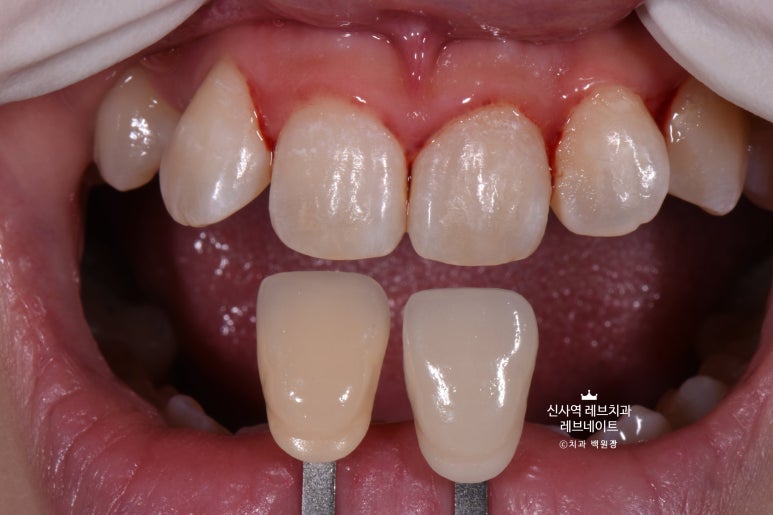

그리고 치아 색상을 측정해 둡니다.

다시 한 번 자세히 보면, 치아 색이 꽤 얼룩덜룩해보이는 것을 아실 수 있을거에요.

사진을 찍어두고 4개를 신중하게 골라야만 했습니다......

그래도 가운데 앞니는 배열이 고르고, 모양도 괜찮은 편이었기에

위에 표시해 둔 4개의 치아를 모양을 최대한 잡아서 한 번 예쁘게 연출을 해보기로 했습니다.